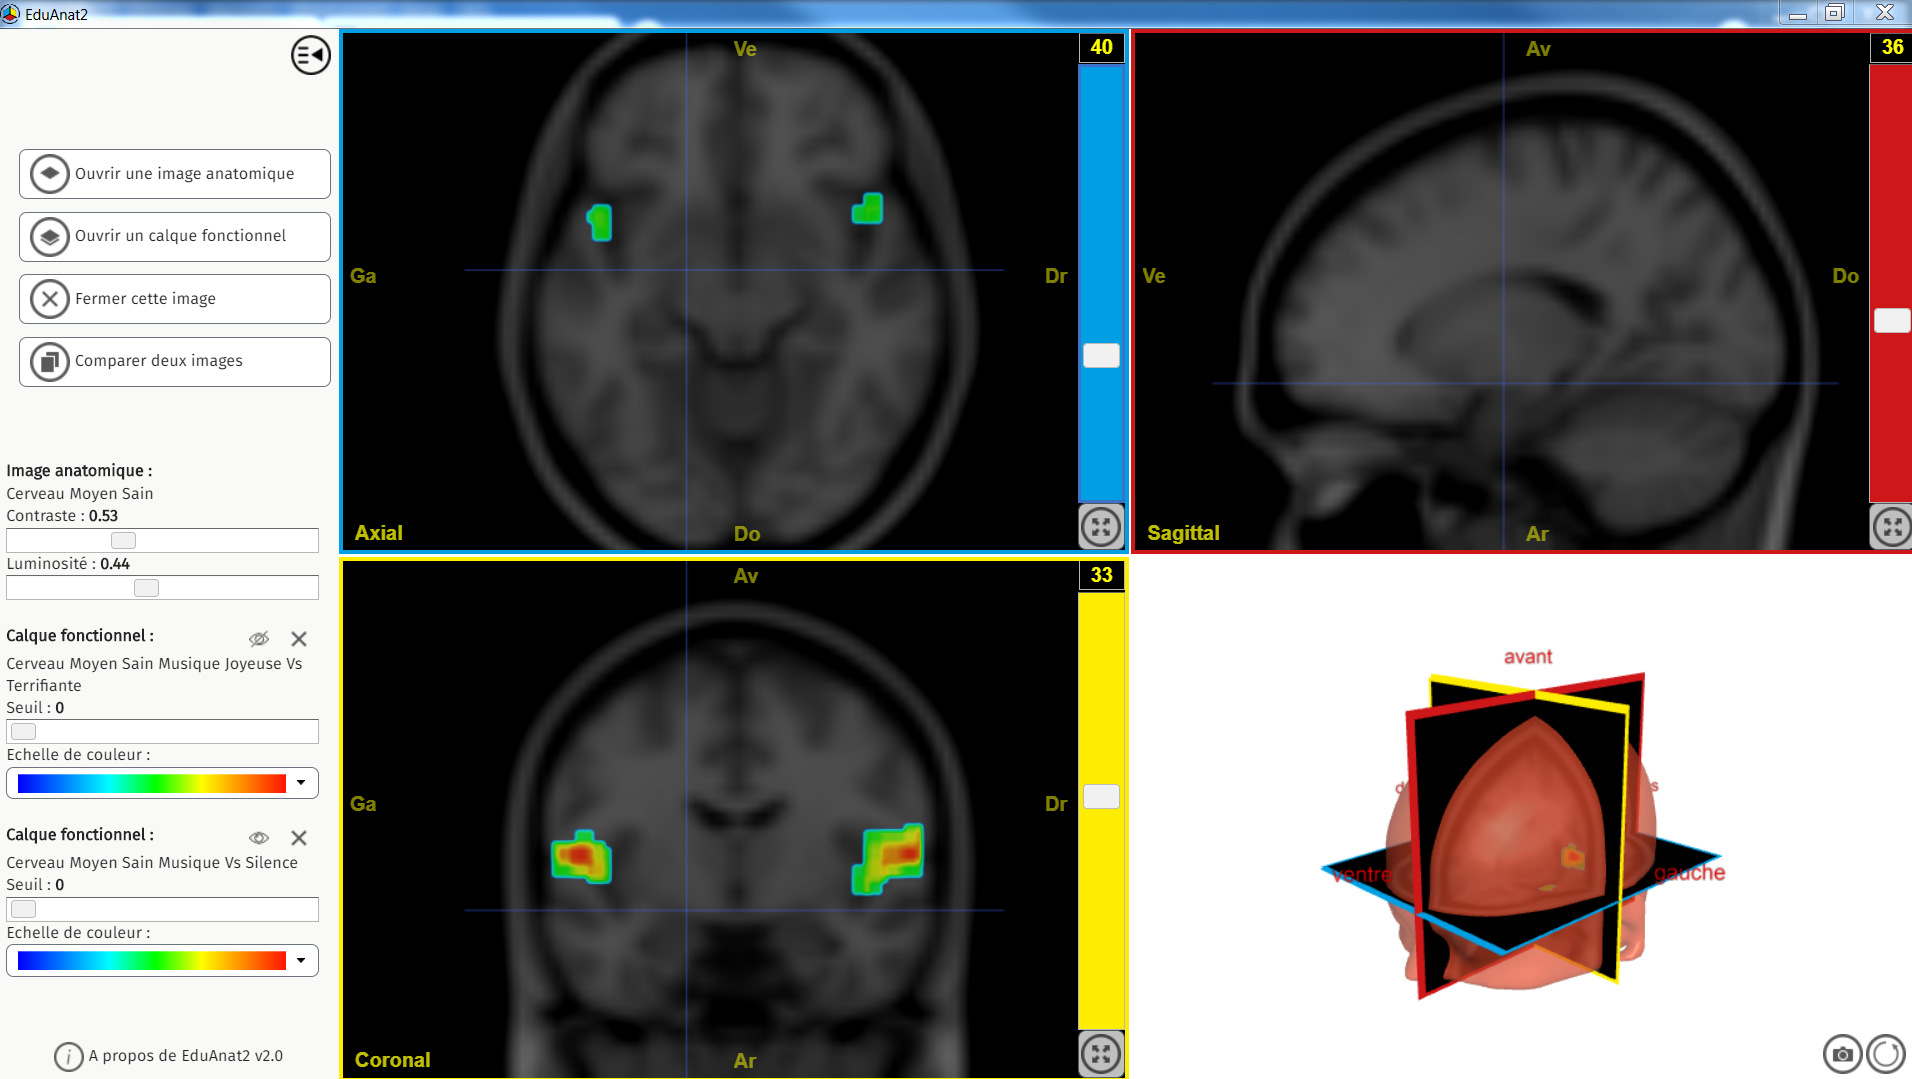

Stress musique versus silence